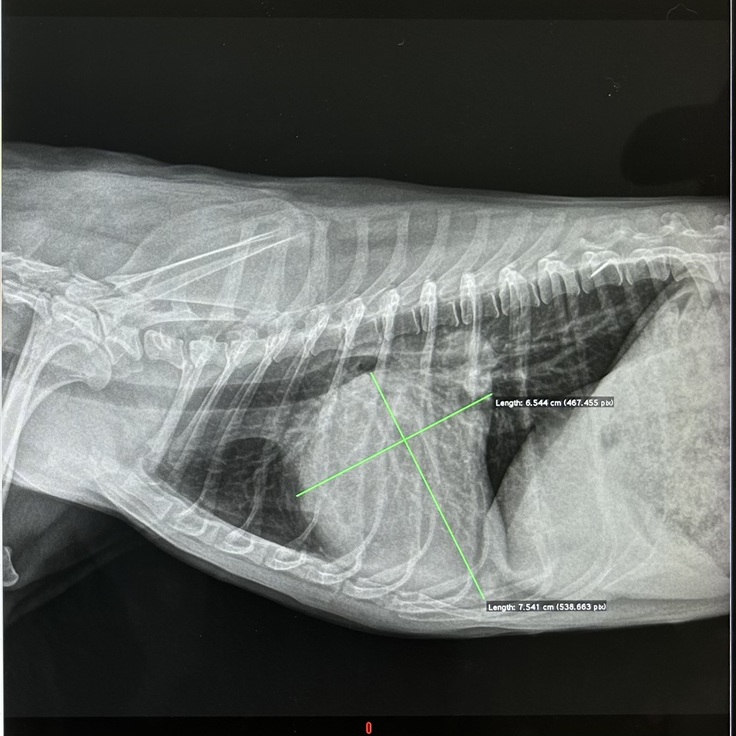

・前回のレントゲンです。

最初の写真と比べクッキリとしています。黒い部分もより多いです。

心臓病でない子は心臓はもっとくっきり見えるそうです。